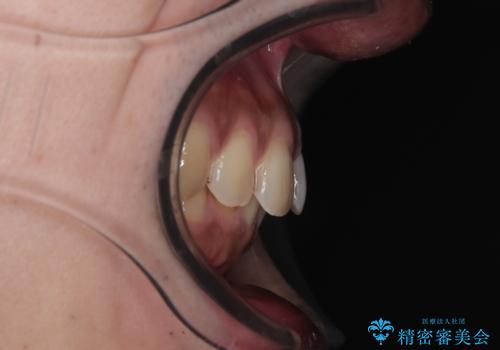

- 上の前歯の正中離開(すきっ歯)と、下顎前歯部の叢生(デコボコ)を主訴に来院された患者様の症例です。

「目立ちにくい装置で治療したい」とのご希望があり、透明のマウスピース矯正であるインビザラインを用いて矯正治療を行いました。